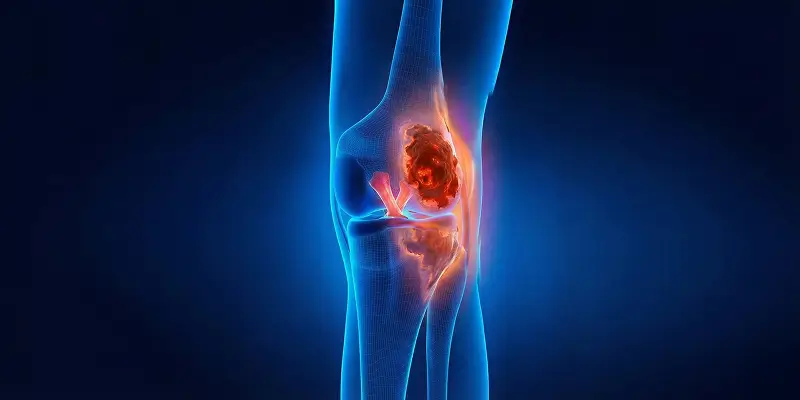

Kemik tümörü (kanseri) nedir, kaç çeşittir? İyi huylu ve kötü huylu kemik lezyonlarına genel bakış ve Dr. Arıkan'ın tedavi yaklaşımı.

Gece artan kemik ağrısı, geçmeyen şişlikler ve sebepsiz kırıklar kemik tümörü habercisi olabilir. Erken tanı hayat kurtarır, belirtileri öğrenin.